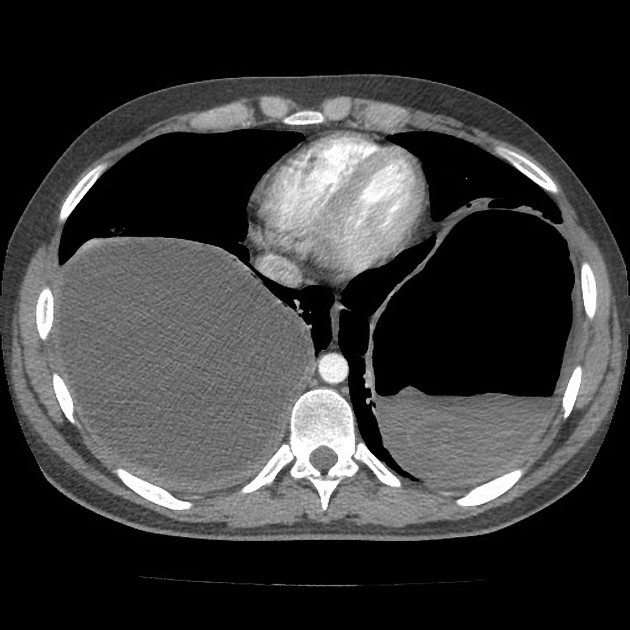

75 ANOS DE IDADE, REFERE DOR TORÁCICA

duplo contorno da borda cardíaca esquerda devido a dilatação da aorta ascendente

ANEURISMA DE AORTA ASCENDENTE